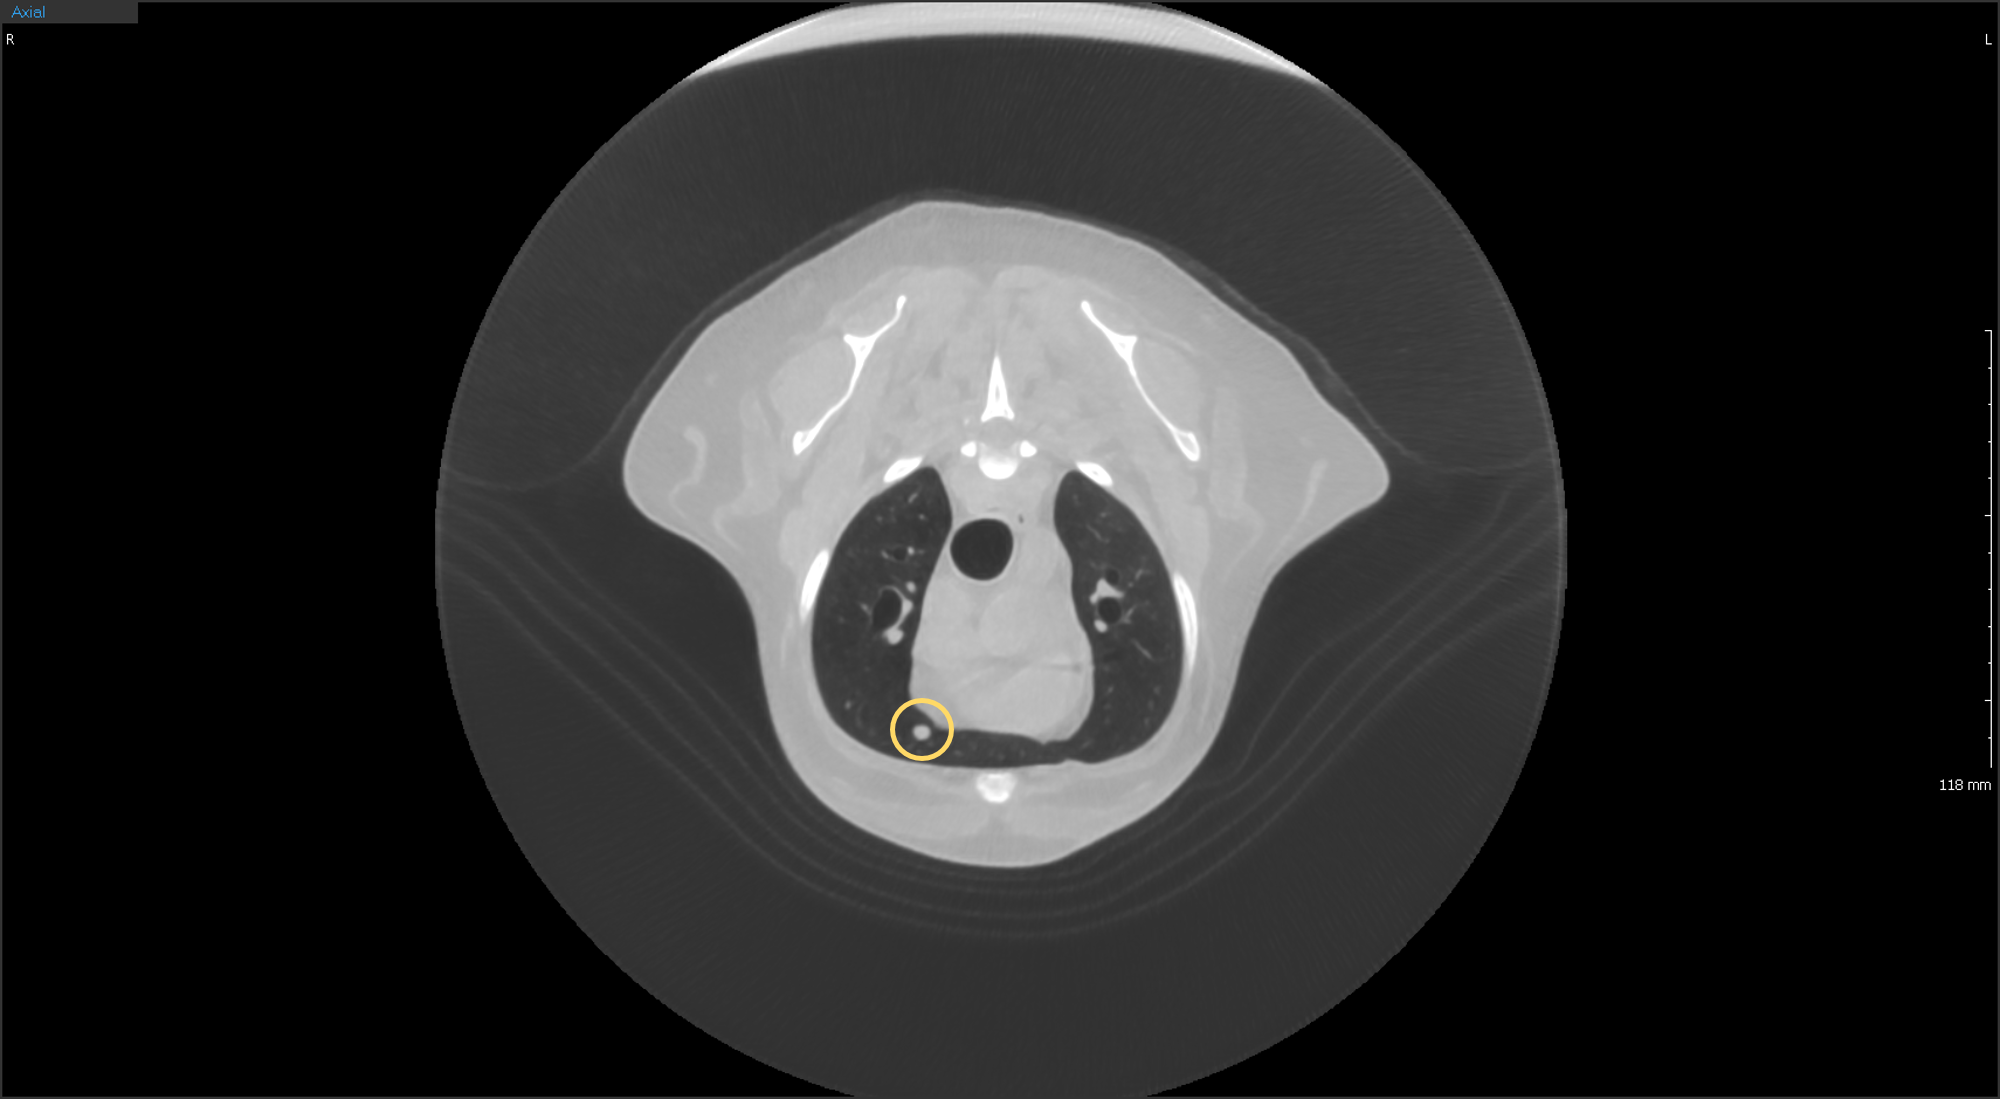

CT

연산동물의료센터의 CT검사는 짧은 촬영으로도

정밀한 3D 입체영상을 얻을 수 있습니다.

“15분에서 30분 정도의 빠른 촬영 시간으로 마취 부담 최소화”

수의학에 최적화된 동물전용 CT

반려동물의 안전을 생각한 선량 CT

인체 CT보다 빠르게 촬영 & 영상 확인 가능

내과, 정형외과, 치과, 안과, 이비인후과까지 다양한 영역 진단 가능

흉부심장 및 대형 혈관, 폐 실질 및 기관, 기관지

폐 CT

폐결절 CT

폐결절

흉부 CT

흉부